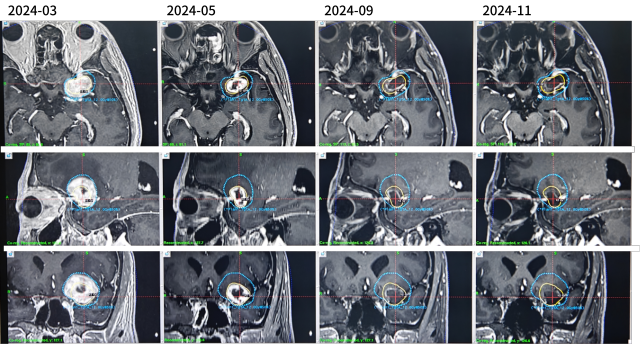

脑转移的治疗

2024-04-至今

三线:伏罗尼布+依维莫司

脑转移放疗

治疗结局:脑转移评估 强化灶消失